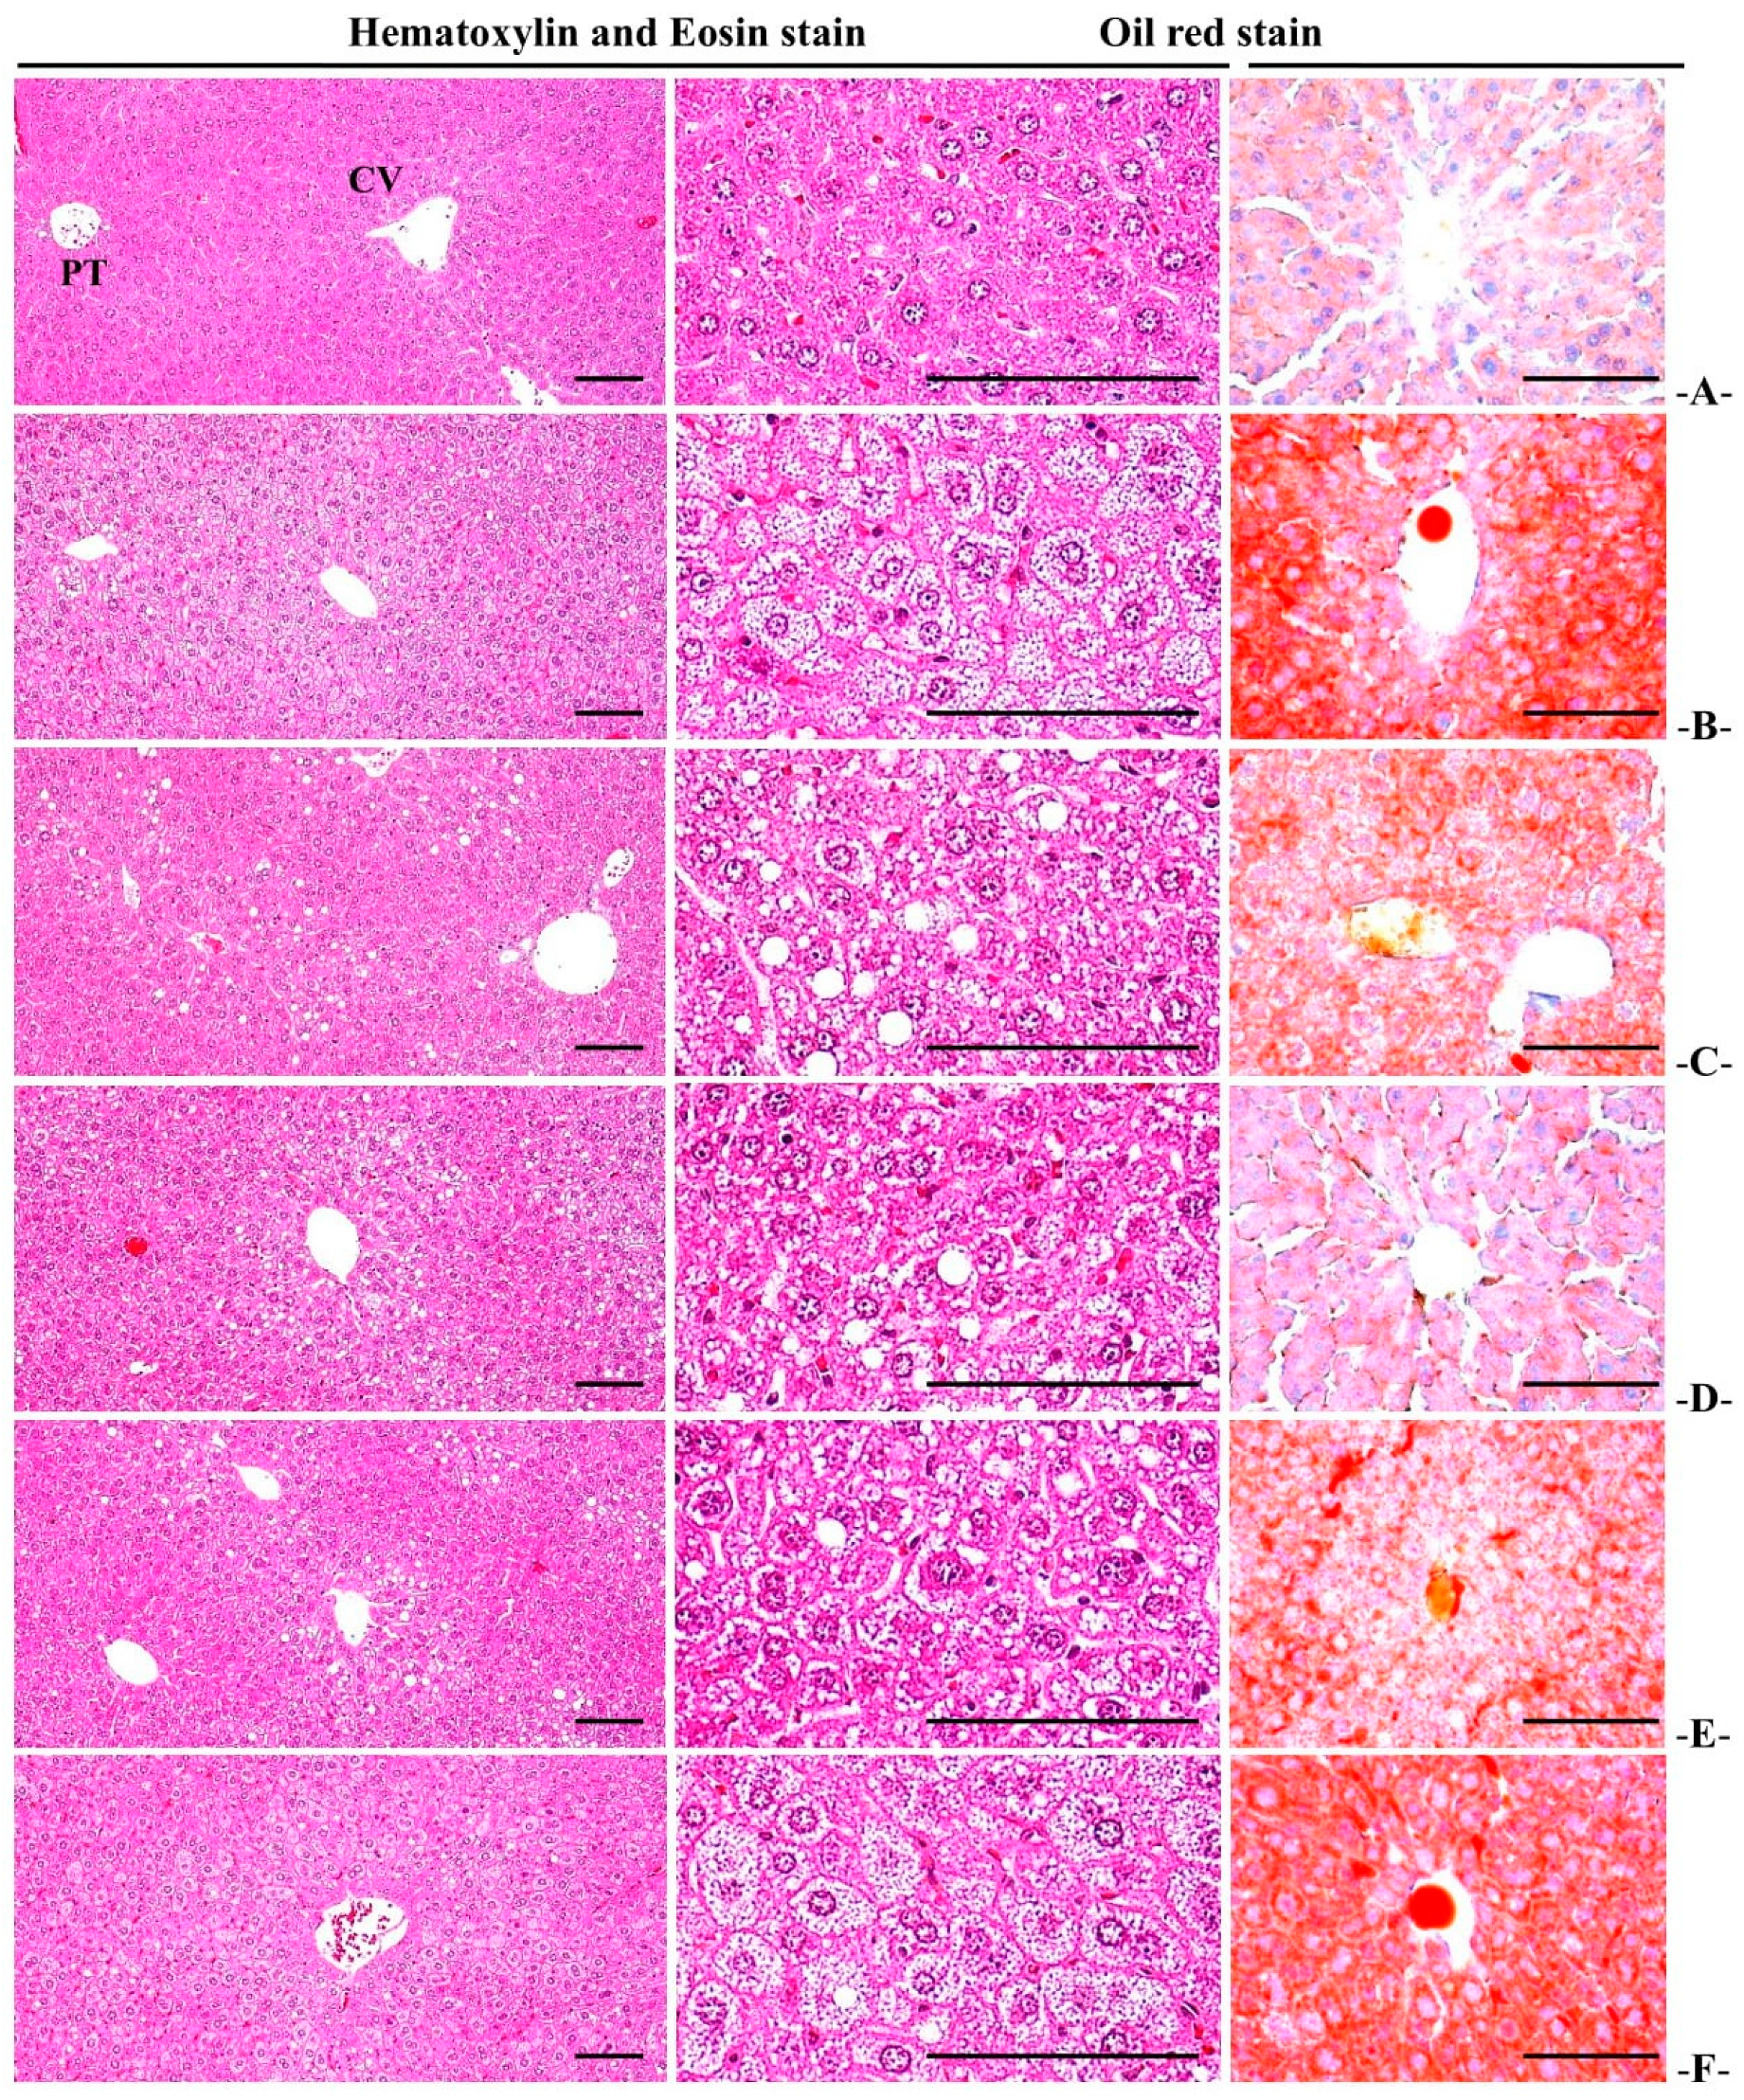

3.5.3. Histopathological Changes in Liver Fat Change Rate

3.5.4. Histopathological Changes in Liver Cell Diameter

| Items Groups | Liver Steatosis (%/mm2 of Hepatic Tissues) | Mean Hepatocyte Diameters (μm/cell) | Degenerative Renal Tubule Numbers (%) |